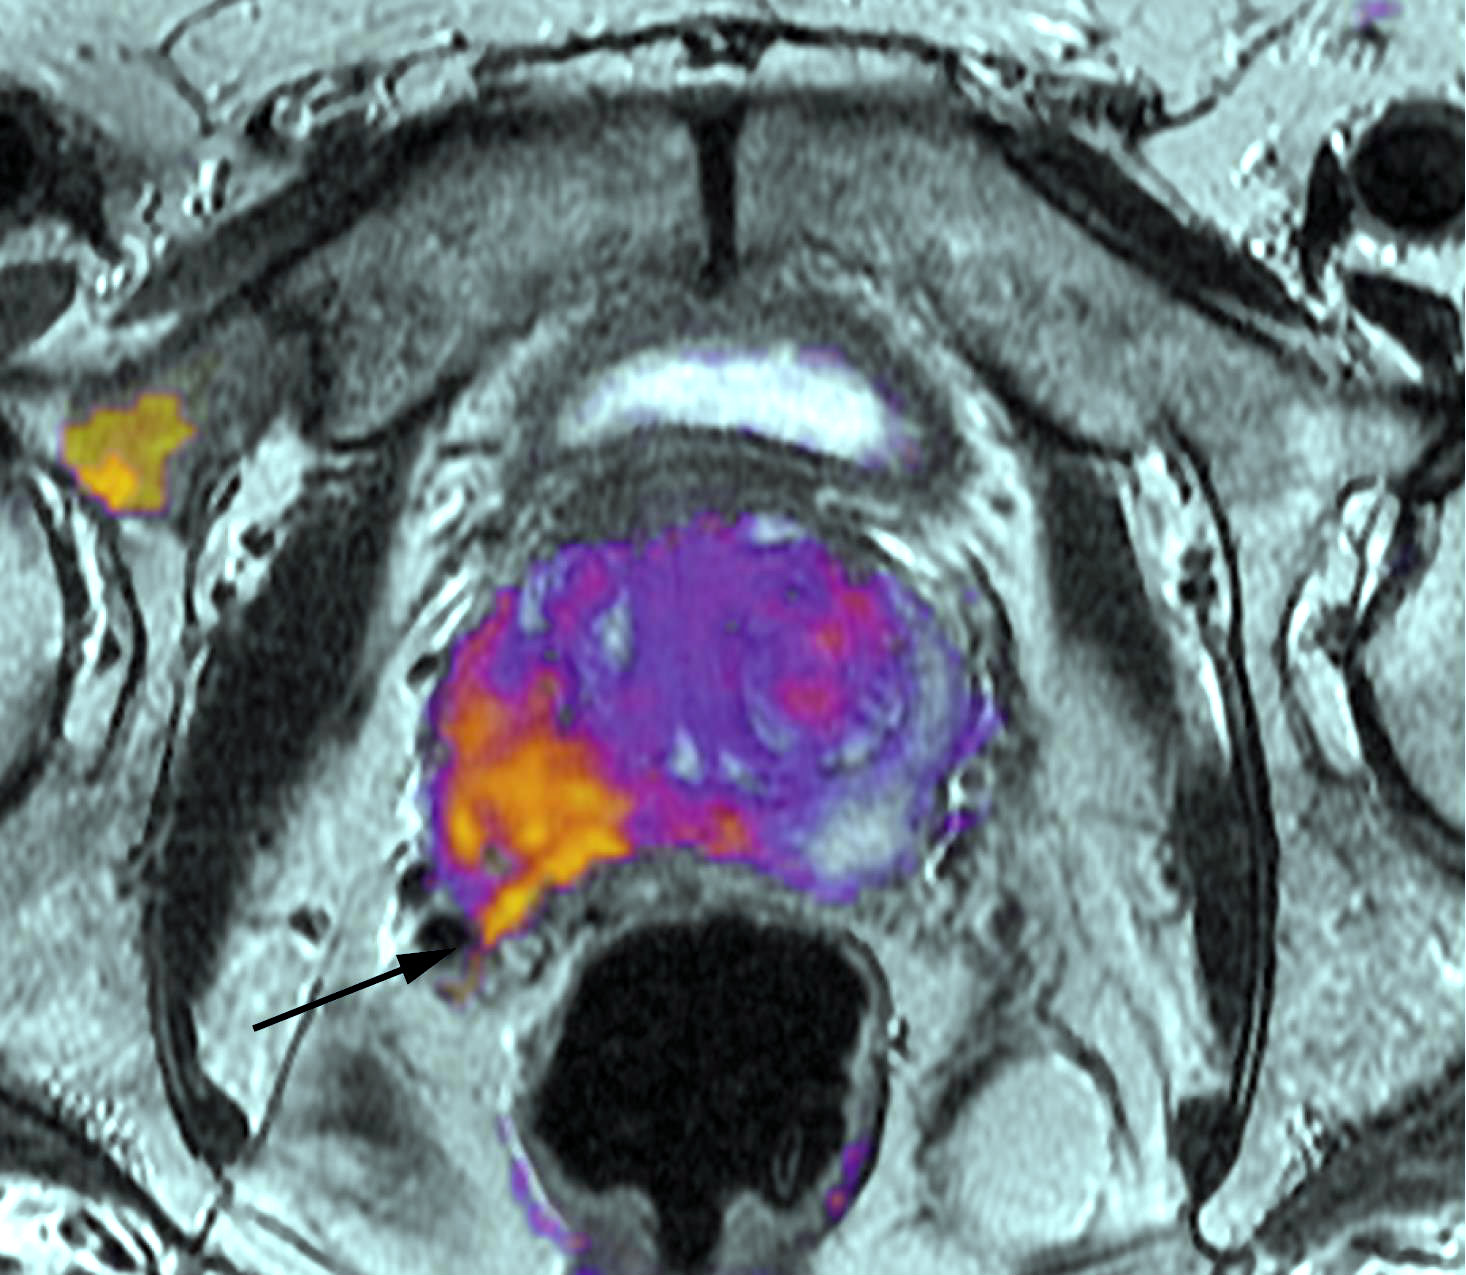

Carcinoma de próstata: novedades terapéuticas

Un ensayo clínico muestra aumento en la sobrevida del cáncer metastásico sumando quimioterapia a la terapia de deprivación androgénica. En otro estudio, la mitoxantrona no fue eficaz luego de la prostatectomía de tumores de altor riesgo sin metástasis. Journal of Clinical Oncology, abril de 2018